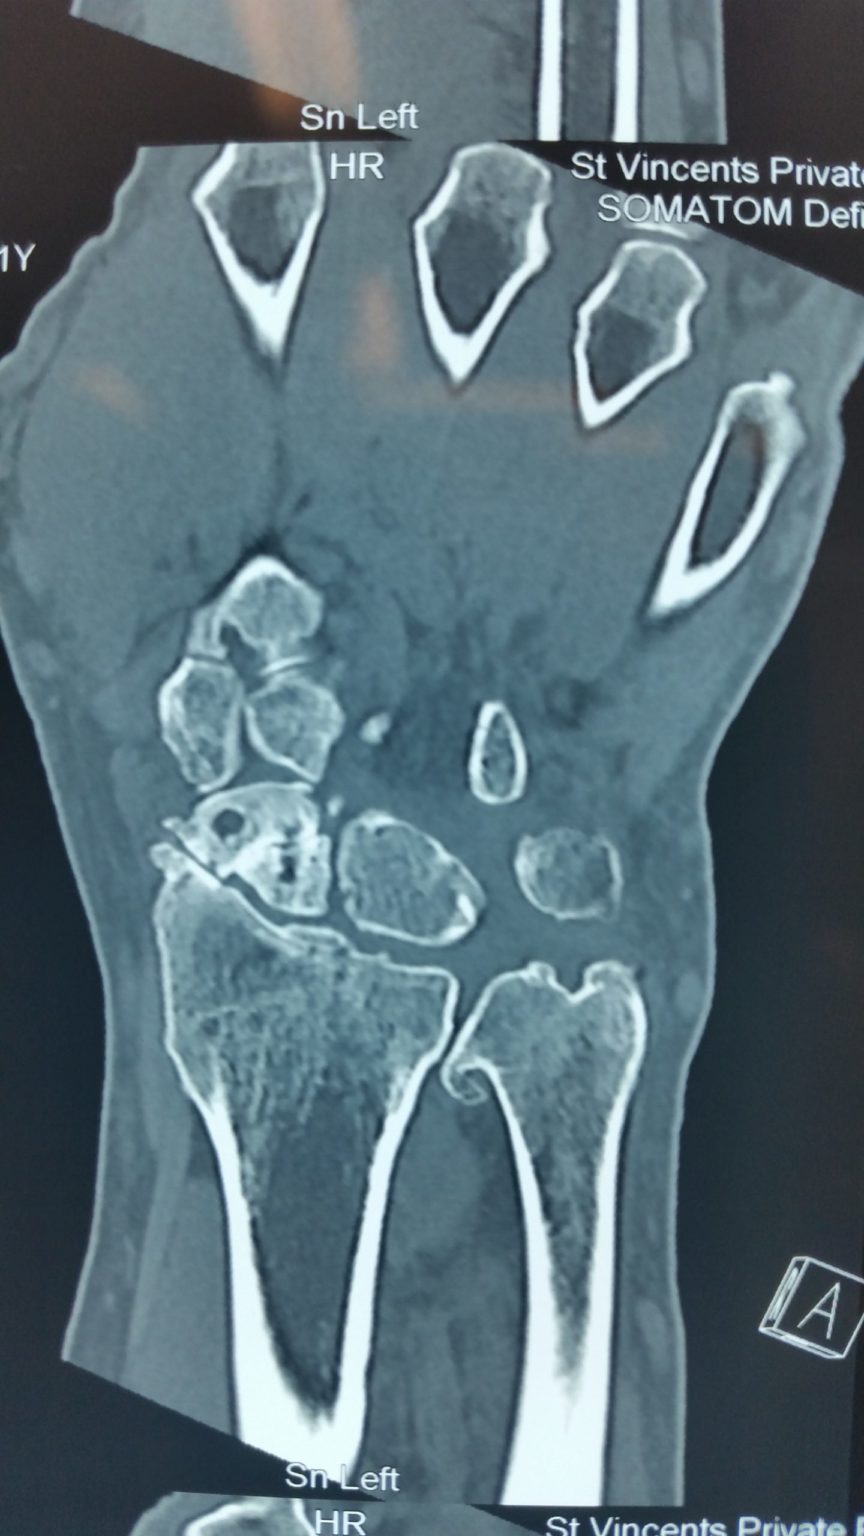

Types of Hand & Wrist Fractures Ladan Hajipour Can You Play Sports With A Scaphoid Fracture scaphoid fractures are the most common carpal bone fracture, often occurring after a fall onto an outstretched hand. surgical management of scaphoid fractures can provide significantly improved rrs and rts to sport compared. this information leaflet has been given to you to provide some useful advice while your wrist is immobilised in a cast. there are. Can You Play Sports With A Scaphoid Fracture.